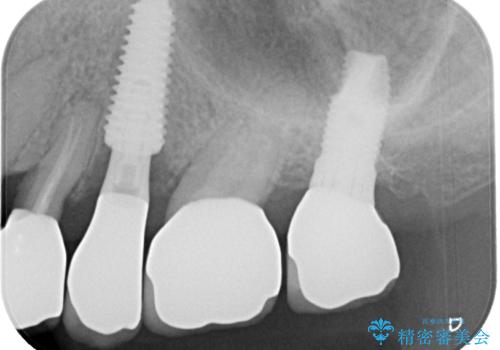

破折によりクラウンの外れてしまった奥歯 抜歯即時埋入で短期間インプラント治療

- 奥歯に装着していたクラウンが外れてしまったとのことで来院された患者様です。

診察したところ、歯根に破折線が確認され抜歯が必要な状態でした。

歯肉や歯槽骨の状態は良好であったため、抜歯即時埋入インプラントによる補綴治療を行うこととしました。

最小の来院回数で短期間で治療を終えることができました。